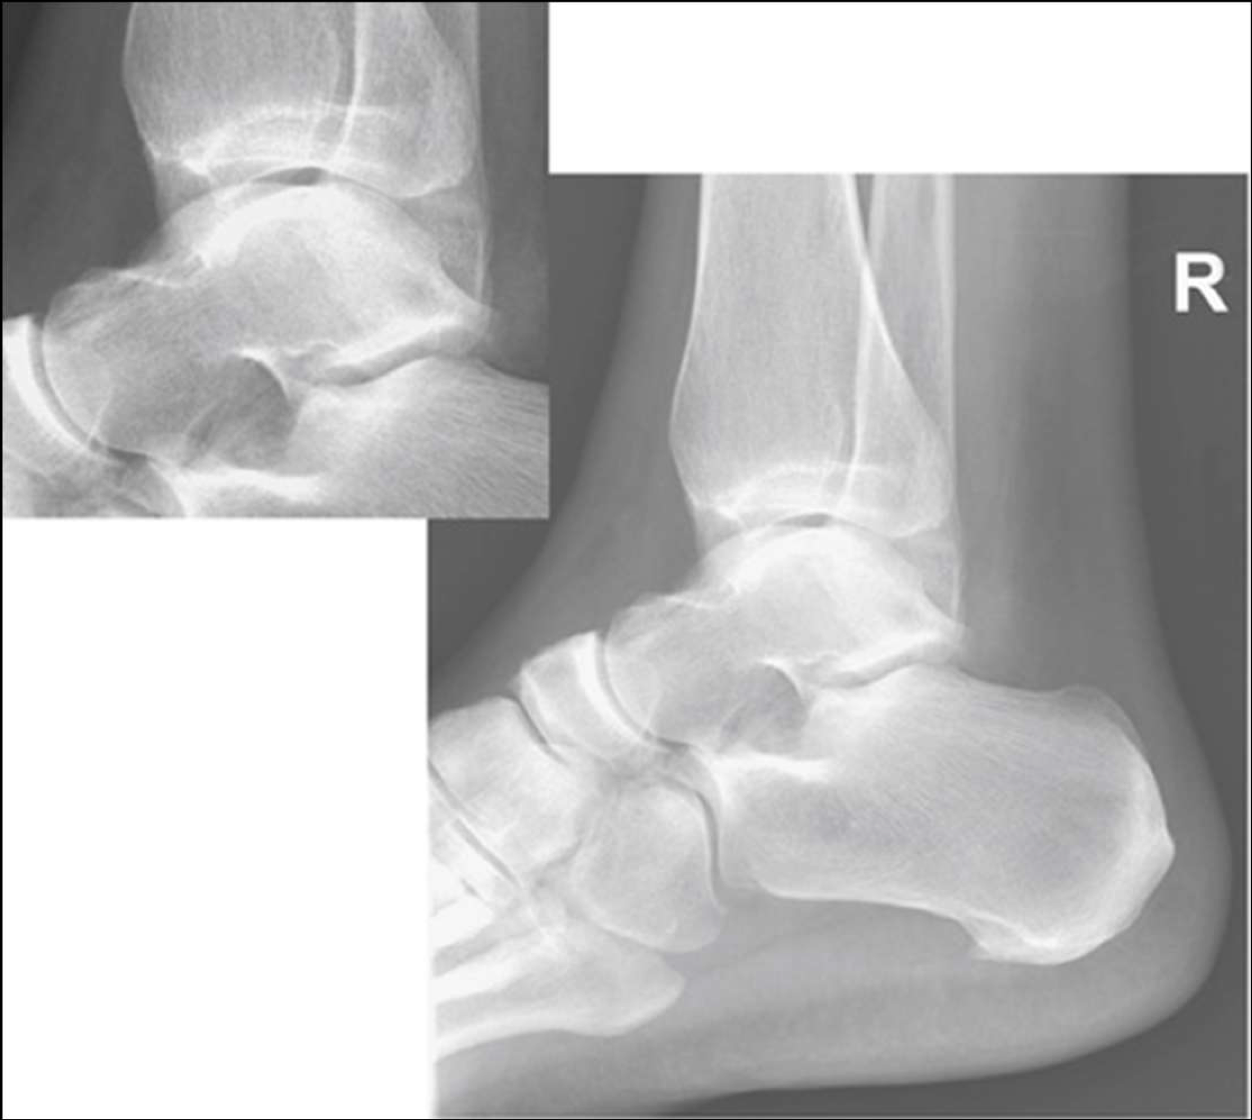

is this lateral ankle over or under rotated

under

over rotated